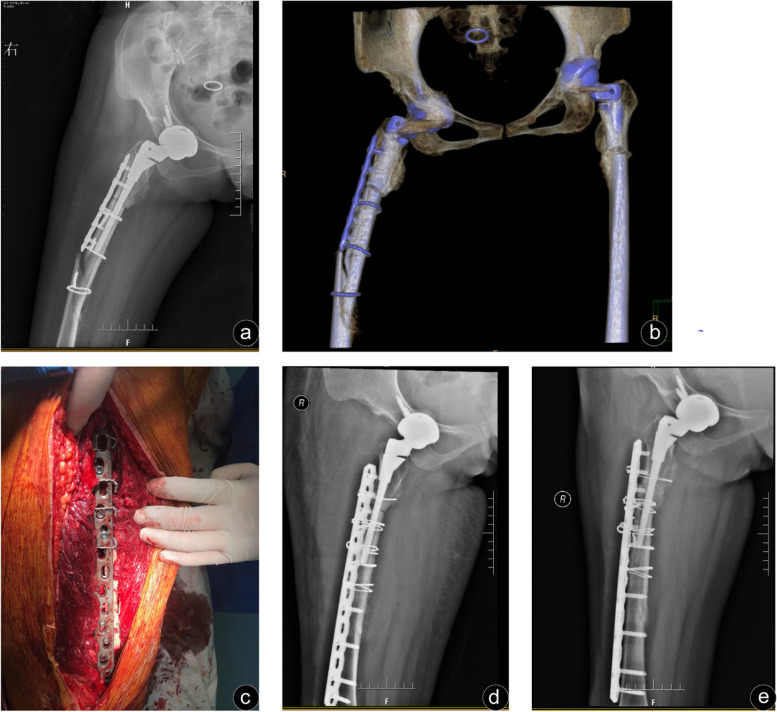

Fig. 2.

A 41-year-old female who sustained a Vancouver type B1 fracture 5 months after primary total hip arthroplasty due to Crowe type IV hip dysplasia. a and b Preoperative anteroposterior X-ray and three-dimensional reconstruction of the femur showed an oblique fracture of the distal right femoral stem. c Locked compression plate and encircling steel wire were used for fixation during operation. d The anteroposterior radiographs on the third day after the operation showed satisfactory fracture reduction, good alignment and normal pseudographs. e Anteroposterior radiographs 6 months after the operation showed distal union of the fracture, but malunion at the proximal osteotomy with a 15-degree varus deformity

In the two groups of postoperative complications, there was a possibility of dislocation taking into account the intraoperative dislocation of the hip joint. No dislocation patients occurred in either group. One patient experienced incision infection after operation. One patient in Group B presented with persistent incision exudation, no fever, local red or other signs of infection. And the clear reddish liquid could be squeezed out during daily dressing change, but the bacterial culture was negative. One week later, incision debridement combined with intravenous antibiotics was performed, and the wound finally healed. One patient in Group B needed to be operated again due to the superficial hematoma in the incision, and the wound healed after drainage and wound compression dressing. Group A patients with nonunion fractures were transverse fractures with medial cortical discontinuity, which were fixed by Wagner SL stem (Zimmer, Warsaw IN, USA) combined with cortical allogeneic. It is worth mentioning that the patient who underwent total hip arthroplasty and subtrochanteric shorting osteotomy due to Crowe type IV Developmental dysplasia of hip (DDH) sustained a Vancouver type B1 fracture (Fig. 2a, Fig. 2b) and a standard ORIF regimen was conducted without cortical strut (Fig. 2c, Fig. 2d). As a result, she suffered from the malunion with 15°malunion at the osteotomy site (Fig. 2e) and had a poor function (HHS score 65), but no further revision was performed as economic condition (Fig. 2). There were no cases with deep vein thrombosis in the two groups during the perioperative period, and no cases with screw breakage or femoral stem loosening in the last follow-up.